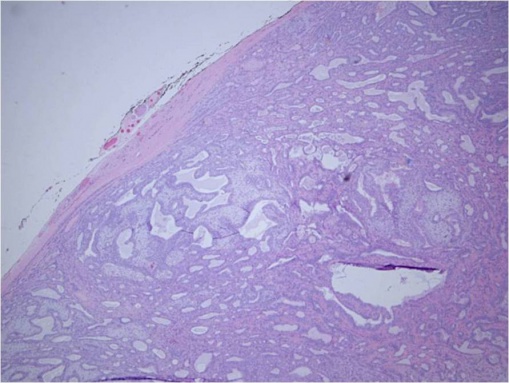

Adenoid cystic carcinoma (ACC) is characterized by solid areas or cords of bland-appearing malignant epithelial cells. The infiltrative borders of the epithelial areas can be distinguished from the surrounding connective tissue and typically show perineural invasion.[1] Immunohistochemical staining may be used to identify perineural invasion by identifying neurofilaments.[13] Adenocarcinoma and PA present myoepithelial cells in the surrounding connective tissue.[1][13] ACC can be further subdivided into histopathologic subtypes: cribriform or 'Swiss cheese', sclerosing, basaloid, comedocarcinoma, and tubular types.

© 2019 American Academy of Ophthalmology; Images obtained from AAO: https://eyewiki.aao.org/Adenoid_Cystic_Carcinoma_of_the_Lacrimal_Gland